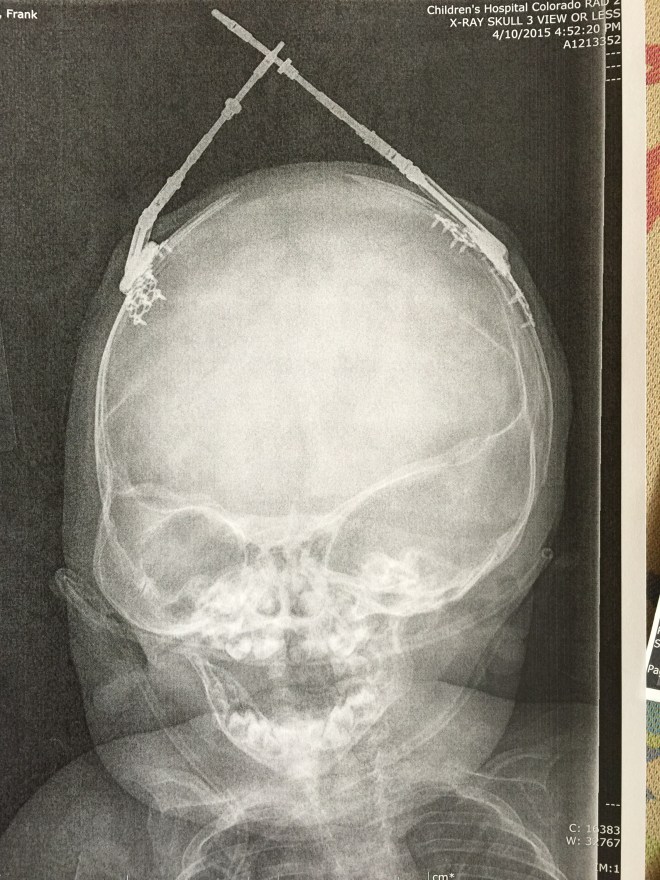

Isaac has been doing great. There was a concern a few weeks after we brought him home. Part of his incision had opened up and the surgeons were concerned that it wouldn’t heal on its own. They had contemplated going back in and closing it up and possibly taking out the plate that was in that area. They decided to give him another week to see if his body would heal up and avoid another surgery. Well, he must not want to go into surgery because the incision healed and the following week we were in they were able to remove the stitches. He does still have his Broviac Line and is still getting heavy antibiotics every night infused through the line. He will continue with the infusion antibiotics until his next surgery. He will be having surgery on his palate and his first finger release in about a month or two. We are still waiting to hear from the scheduler on a date.

The Craniofacial department has a camera that takes a 3D picture. These next two pictures show a comparison of Isaac’s head from the beginning of May, before his last surgery. The pictures on the right are from May and the pictures on the left are from a few weeks ago. You can really tell a difference in the shape of his head.